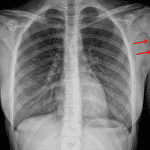

Age: 15

Sex: Female

Indication: Fever, cough

Findings

- No focal airspace disease, pleural effusion, or pneumothorax

- Normal size and configuration of the cardiothymic silhouette

- Permeative lesion in the proximal left humerus with adjacent periosteal reaction

Diagnosis

- Osteosarcoma (corner finding)

No focal airspace disease, pleural effusion, or pneumothorax.

Normal size and configuration of the cardiothymic silhouette.

Permeative lesion in the proximal left humerus with adjacent periosteal reaction, concerning for an aggressive infection or neoplasm. Recommend dedicated humerus radiographs for further evaluation.